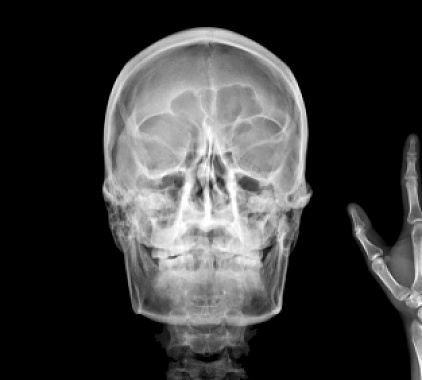

Сначала администратор уточняет данные, затем рентгенлаборант приглашает в процедурный кабинет. Проведение занимает 5–10 минут, основное — правильно уложить пациента и зафиксировать положение головы. Используется медицинский рентгеновский аппарат с цифровым детектором: так снимок сразу видит врач на мониторе. Возможны следующие варианты выполнения:

- Обзорная. Этот вариант применяют как стартовый. Пациента ставят или усаживают, просят ровно дышать и не глотать. Обзорная рентгенография носоглотки дает общее представление об анатомии: видны контуры кости, носовой полости и тени мягких тканей. Удобно при первичной оценке и в неотложных ситуациях.

- Рентген носоглотки в боковой проекции. Голова слегка поворачивается, чтобы луч прошел сбоку. Такая проекция лучше всего показывает высоту носоглоточного свода, размеры аденоидов, степень перекрытия хоан, дает оценку просвета носоглотки. Именно боковая позиция помогает визуализировать те самые «тени», которые мешают воздуху проходить.

- По Колдуэллу. Пациента просят наклонить лоб к кассете под углом. Проекция по Колдуэллу улучшает видимость лобных пазух и решетчатого лабиринта, а также их соотношение с областью носоглотки. Полезна, когда врач подозревает комбинированный процесс и хочет оценить верхние отделы носа.

- По Уотерсу. Здесь упор делается на верхнечелюстные пазухи и дно орбит. Положение головы с подбородком у кассеты смещает проекцию так, чтобы придаточные пазухи четче отделялись от костных перегородок, а переход к носоглотке просматривался более свободно. Этот вариант часто добавляют к боковой проекции для комплексной картины.

После снимка врач-рентгенолог готовит заключение. В описании рентгена носоглотки рентгенолог описывает, что именно показывает рентгенограмма, где видны отклонения и что требует внимания ЛОР-врача.

Что считается нормой:

- Просвет носоглоточного свода свободный, контуры ровные, патологических теней нет.

- Тени мягких тканей тонкие, симметричные; костные структуры четкие, без линий перелома.

- Придаточные пазухи прозрачны, уровней жидкости не определяется.

- Носовой ход не сужен, тени хоан свободны.